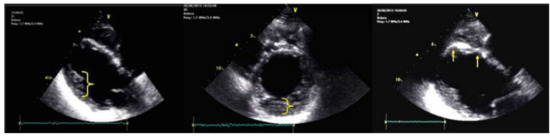

5. Cases Presentation